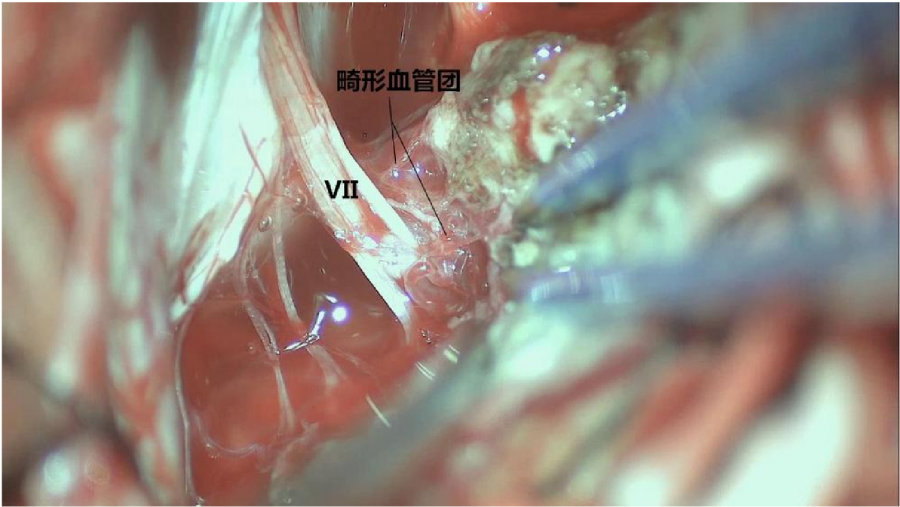

⾏左侧远外侧⼊路脑⼲⾎管畸形切除术,术中所⻅:

3、脑⼲动静脉畸形⼿术切除是注意辨别供⾎动脉与引流静脉,其往往不似其他部位的动静 脉畸形,有叫粗⼤的引流静脉。术中如果不能辨清各⾎管来源与去处,往往会造成不可估量的损失。

4、脑⼲动静脉畸形团周围玩个昂存在复杂的神经及⾎管,操作难度⼤。